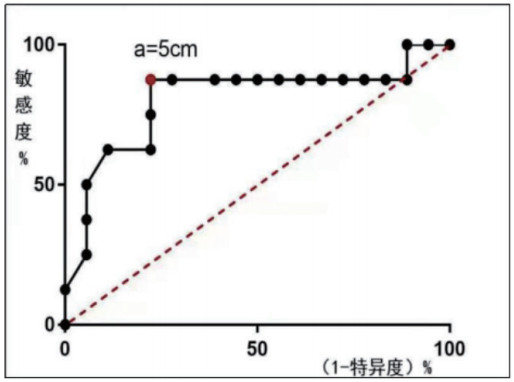

病灶最大径线值(a)亦表现出明显的组间差异,组4平均病灶a显著大于组2、组3(P > 0.05)。以a作为预测是否需后续手术治疗的指标,可取当a=5 cm时获得最佳预测价值灵敏度0.88,特异度0.77,约登指数0.65(图 3)。提示a>于5 cm时需后续进腹手术治疗的概率大。

| 图 3 病灶最大径线值a(cm)预测ROC曲线 |

UAVF的治疗方法包括观察、药物治疗、子宫动脉栓塞和手术治疗[17]。急诊大出血时,有生育要求者可行UAE,无生育要求者可行子宫切除术[9, 13]。目前的研究支持将UAE作为妇产科急症出血中替代手术的首选方法[18-19]。既往研究显示,治疗方式的选择与病灶大小及病灶收缩期峰值(PSV)相关,当子宫动静脉瘘PSV较高且病变较大时,UAE是理想的治疗方法,可反复多次进行[5, 20]。该研究中单纯UAE成功率达92.3%,相关并发症较少,对生育影响小,与文献报道相符[5]。但目前缺乏对病灶大小与治疗方法疗效的研究,潜在风险的PSV值亦无统一标准[5, 15]。本研究得出超声测量病灶大小(V)和最大径线(a)对该病治疗的意义及治疗节点:V>130 cm3或a>5 cm的患者行UAE后再进腹手术治疗(病灶剔除或子宫切除)安全有效,否则容易出现栓塞失败或病情反复。